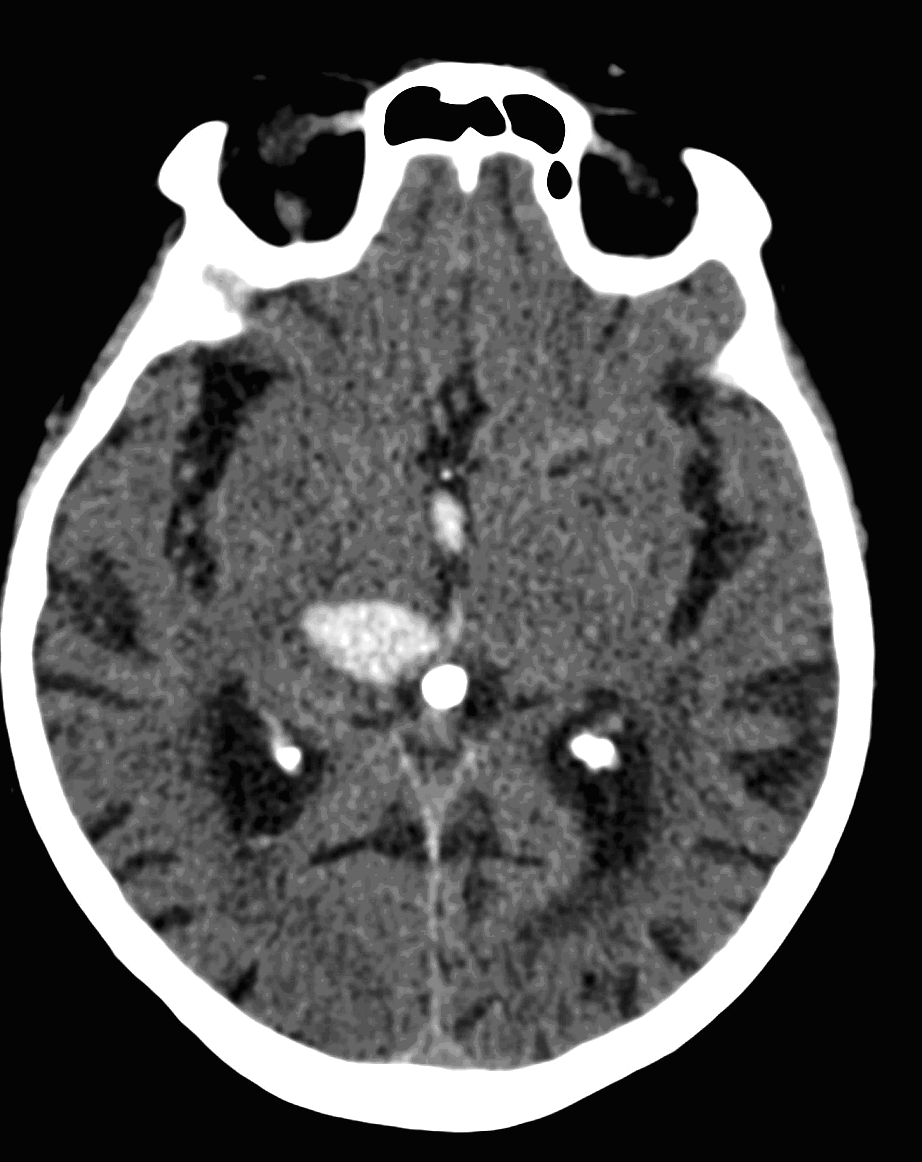

On CT images acute bleeding always presents as hyperdensity. (One has to keep it mind that hyperdensity of the blood is affected by the hematocrit levels, hence making the diagnosis more difficult.) Intraparenchymal blood is dominated by a destructive appearance (mass-effect) and it is surrounded by hypodensity as a sign of perifocal edema. It often breaks into the ventricles. In patients lying in a supine position they collect (sediment) at the occipital horn of the lateral ventricles, creating a hyperdense liquid-to-liquid levels. Later on, the density of blood decreases and shows a peripheral ring or rim-like contrast enhancement without mass-effect.

Although, subarachnoid hemorrhage (SAH) is most often caused by the rupture of a berry aneurysm, arteriovenous malformation (AVM) and trauma can also lead to it. SAH is typically located at the basal subarachnoid spaces, which then propagates along the lateral fissures or it fills up the interhemispheric fissure till the convexities. The main collection of the blood is usually indicative of the source of origin. In cases of parenchymal spread the mechanism, whether it broke in, or it broke out from the parenchyma could represent a differential diagnostic challenge. When accompanied by brain edema, the consequent herniation can result in parenchymal infarcts as well.

CT angiography examination is usually advisory in order to confirm the site of the bleeding. It is also effective when a hemorrhagic tumor is in the differentials, although complete differentiation might only be achieved by follow-up examinations. CTA is also essential in the diagnostics of multiple aneurysms (which are prevalent in 20-30% of the cases based on autopsy reports.) In case of a subarachnoid hemorrhage the consequently developing hydrocephalus and its degree might only be detected on follow-up CT examinations. It is very important to note that an initial brain aneurysm rupture might be followed by a second one within the first 7 – 10 days and the resulting vasospasm carries a much higher risk of mortality than the one at the time of the first SAH. This is why the scrutonius review of the acute diagnostic imaging is essential and it plays a fundamental role in patient treatment. Open brain surgery of the aneurysm (clipping) has been replaced by catheter angiography (DSA) nowadays. The aneurysm is either filled up with thrombogenic coils through its neck or recently bypassing stents are inserted to exclude the aneurysm from the cerebral circulation.